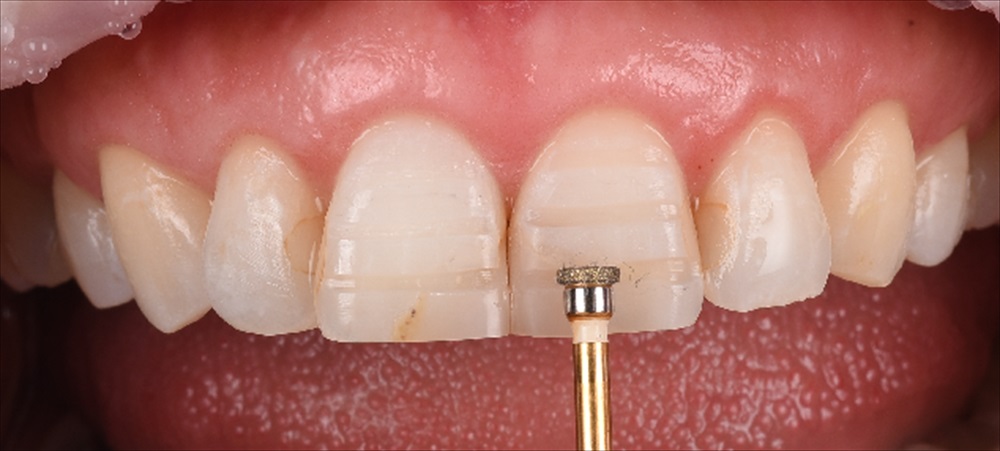

ここから歯をなるべく削らない作戦を技工士の間中とたてガイドを作成

見て頂くと分かると思いますが、前歯2本のみ0.7削り他はノンプレップ(削らない)です。

形成量はこの感じ。